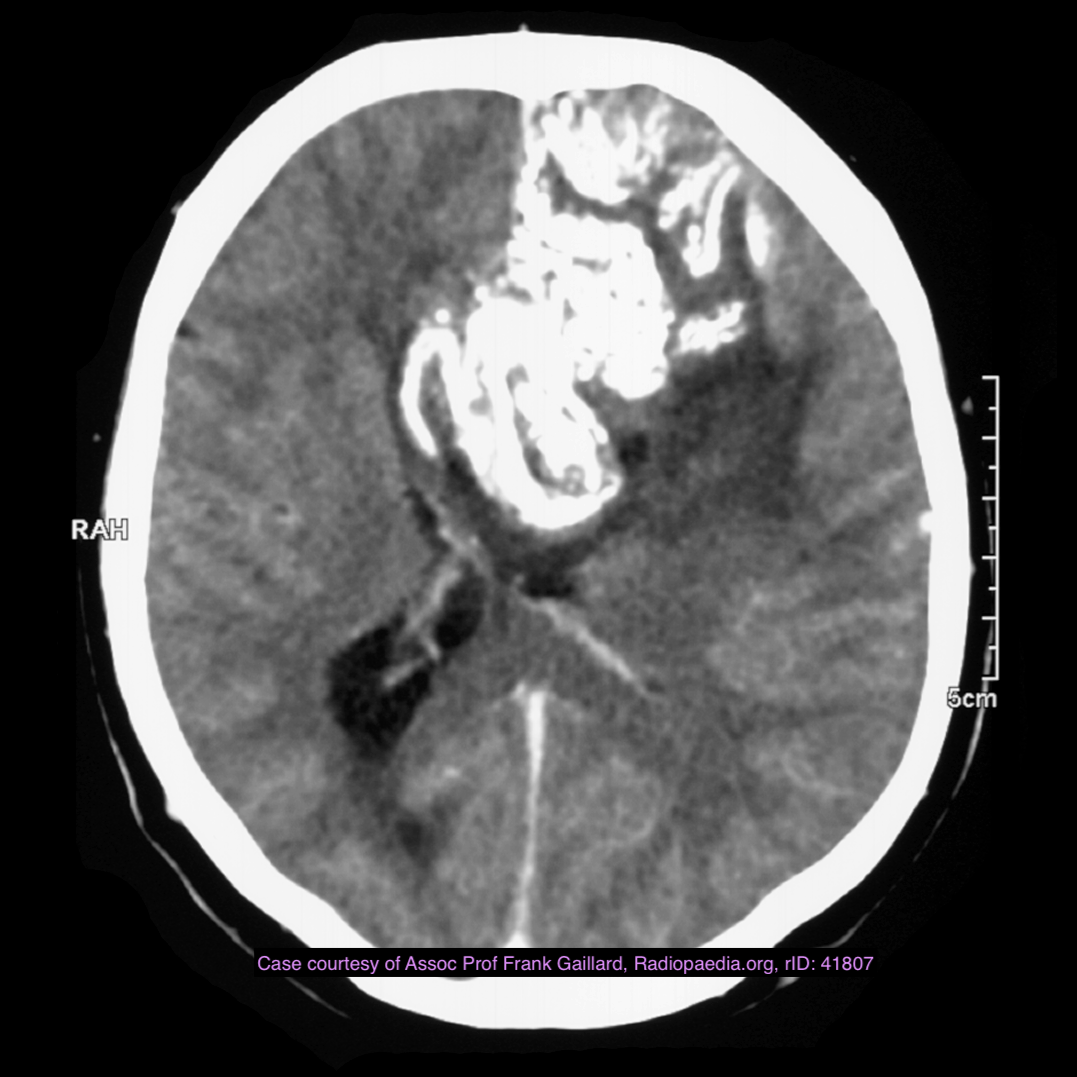

Note the multiple sites of oedema and haemorrhage, involving the brain stem and corpus callosum as well as subcortical white matter and left cerebral peduncle. High FLAIR signal is also seen in the dorsal midbrain. EVD insitu.

Case Discussion

Diffuse axonal injury can be subtle on CT but have devastating consequences for the patient. This is a case of grade III injury (involvement of brainstem) and carries a poor prognosis.

Diffuse axonal injury (DAI), also known as traumatic axonal injury (TAI), is a severe form of traumatic brain injury due to shearing forces. It is a potentially difficult diagnosis to make on imaging alone, especially on CT as the finding can be subtle, however, it has the potential to result in severe neurological impairment.

The diagnosis is best made on MRI where it is characterised by several small regions of susceptibility artifact at the grey-white matter junction, in the corpus callosum, and in more severe cases in the brainstem, surrounded by FLAIR hyperintensity.

Diffuse axonal injury is characterised by multiple focal lesions with a characteristic distribution: typically located at the grey-white matter junction, in the corpus callosum and in more severe cases in the brainstem (see: grading of diffuse axonal injury).

CT

Non-contrast CT of the brain is routine in patients presenting with head injuries. Unfortunately, it is not sensitive to subtle diffuse axonal injury and as such, some patients with relatively normal CT scans may have significant unexplained neurological deficit 4,5.

The appearance depends on whether or not the lesions are overtly haemorrhagic. Haemorrhagic lesions will be hyperdense and range in size from a few millimetres to a few centimetres in diameter. Non-haemorrhagic lesions are hypodense. They typically become more evident over the first few days as oedema develops around them. They may be associated with significant and disproportionate cerebral swelling.

CT is particularly insensitive to non-haemorrhagic lesions (as defined by CT) only able to detect 19% of such lesions, compared to 92% using T2 weighted imaging 4. When lesions are haemorrhagic, and especially when they are large, then CT is quite sensitive. As such, it is usually a safe assumption that if a couple of small haemorrhagic lesions are visible on CT, the degree of damage is much greater.